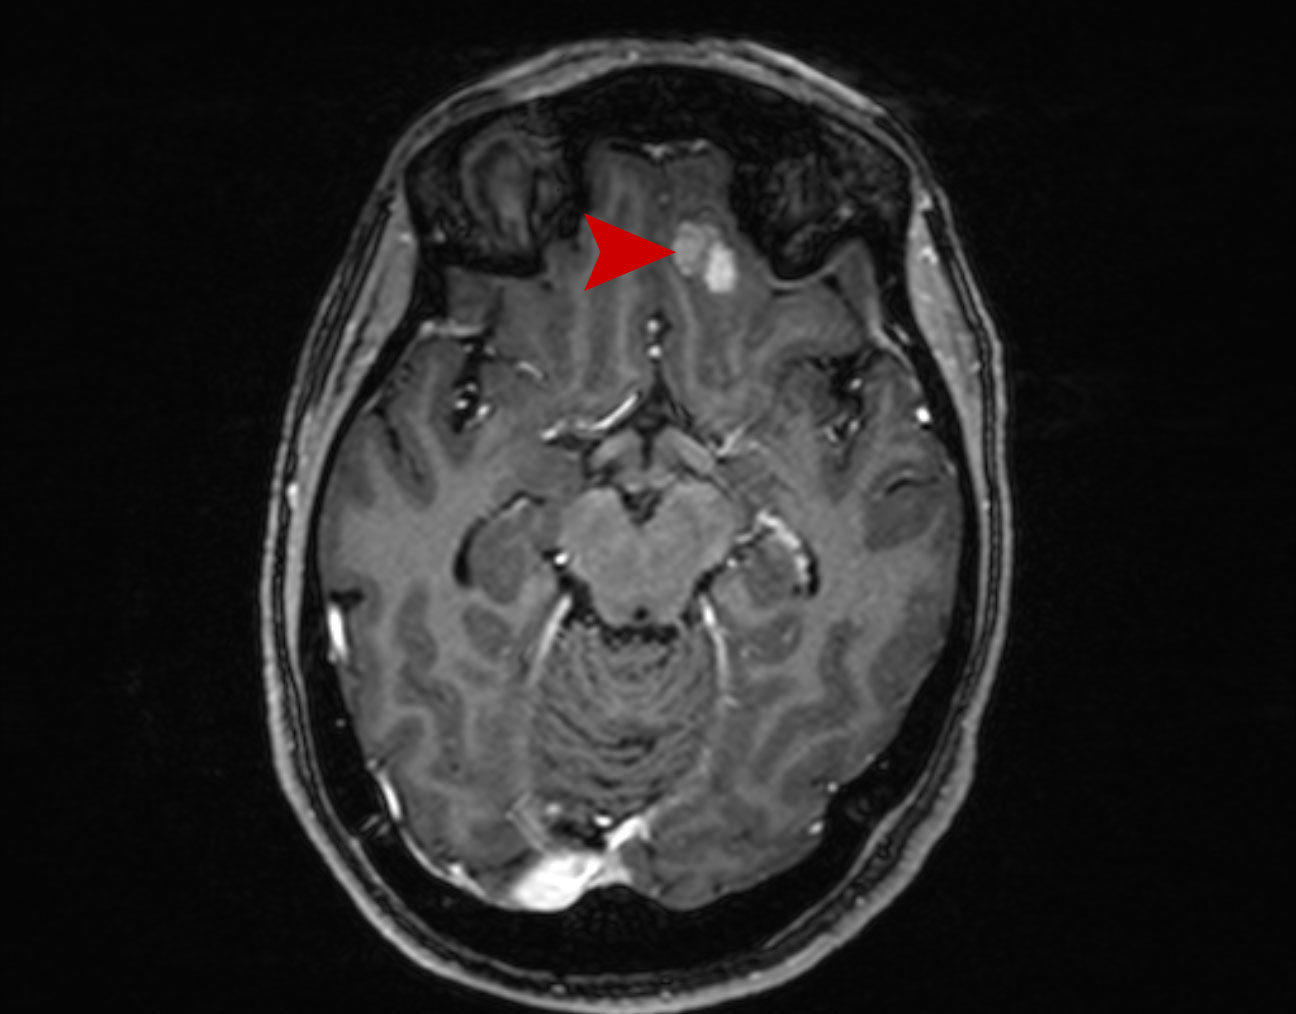

Μετάσταση στον Εγκέφαλο Θεραπεία με CyberKnife #31

Άρρεν 65 ετών με δευτεροπαθή εγκεφαλική εντόπιση αριστερά μετωπιαία από Ca παχέως εντέρου με συνοδό…